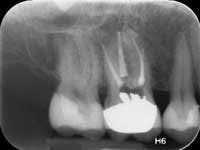

Less than one-half of the coronal tooth structure remaining (Figs. 1-6)

It is my opinion, regardless of the other factors present, that it is still advisable to place a post or posts in such teeth. Endodontically treated teeth with less than one-half of the coronal tooth structure remaining have a reduced chance of long-term service, and patients should be so advised as the treatment plan is developed.